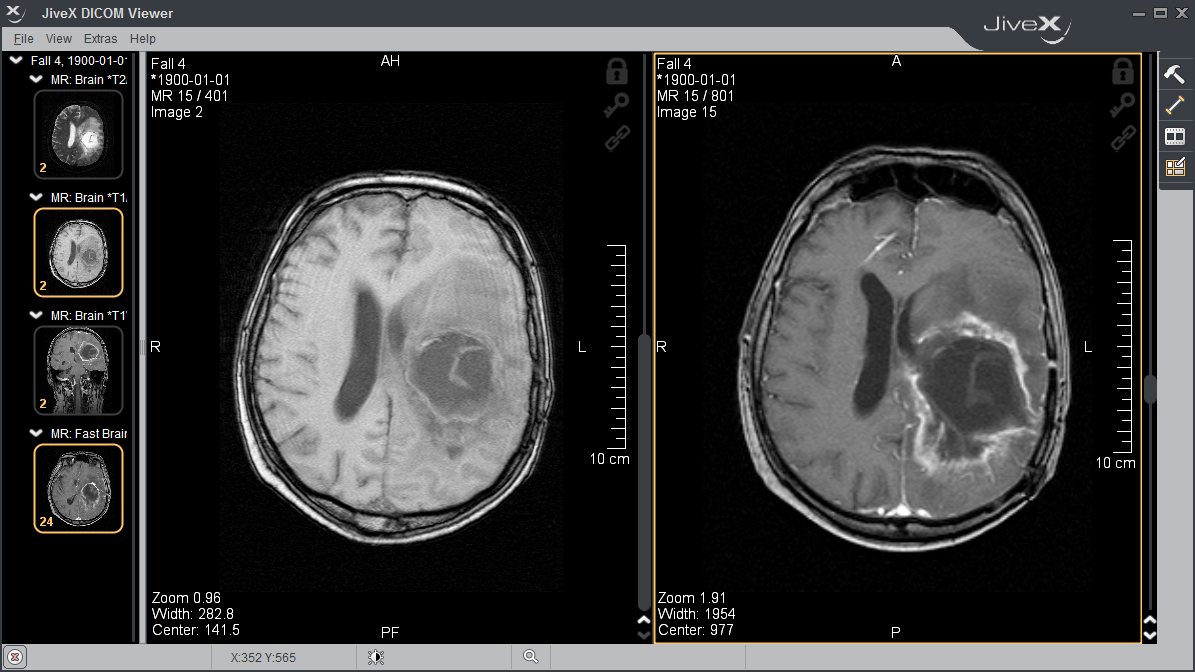

Microdicom dicom viewer is equipped with most common tools for manipulation of dicom images and it has an intuitive user interface. Store, view, collaborate, and share your medical imaging files. With help of groupdocs.viewer app.

Our software can be used. 3d option including the standard 2d features and measurements, has advanced multiplanar reconstruction (mpr) features, like: Athena dicom essential marks a new generation of software to view and manipulate medical images.

The dicom viewer package is capable of handling all dicom. Nstantly view dicom files with our free dicom viewer. Your data is already displayed with the integrated web viewer.